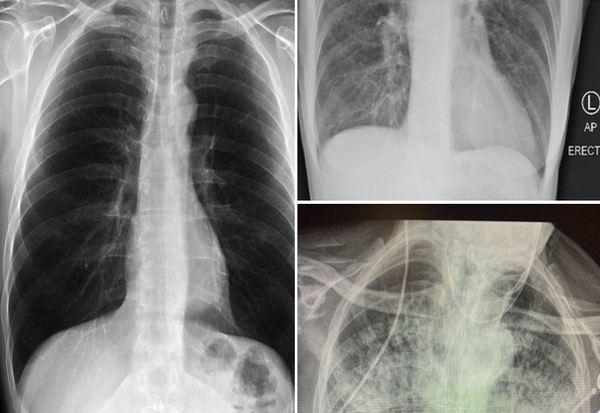

Но неодамна докторка од Тексас која лекувала илјадници пациенти заболени од Ковид-19 сподели неколку вредни сознанија за болеста и нејзините последици по споредувањето на три ренгденски снимки на белите дробови: една од здрав пациент, една од пушач и една од пациент со Ковид-19.

Д-р Британи Банкхед-Кендал, асистент-професор на Центарот за здравствени науки на Техничкиот универзитет во Тексас, на „Твитер“ сподели дека белите дробови кај пост-ковид пациенти се полоши од белите дробови на пушачи кои таа досега ги видела.

Докторката објави фотографии од трите рендгенски снимки за да укаже на разликите.

Белите дробови на здравиот пациент се чисти и имаат доста црн простор, што покажува дека личноста може да вдиши голема количина на воздух.

Белите дробови на пушач покажуваат замагленост.

Третата слика ги прикажува белите дробови на пациент кој боледувал од Ковид-19. Може да се забележи дека снимката е речиси бела, што значи дека белите дробови се сериозно оштетни.